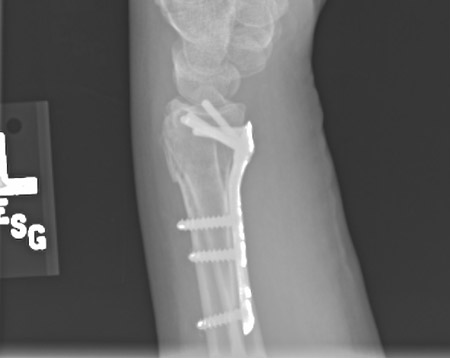

O monitoramento da função do nervo mediano deve ser mantido durante todo o período pós-operatório.[Figure caption and citation for the preceding image starts]: Fixação com placa, após redução aberta, com placa e parafusos colocados em posição volarDo acervo do Dr. Chaitanya S. Mudgal [Citation ends].